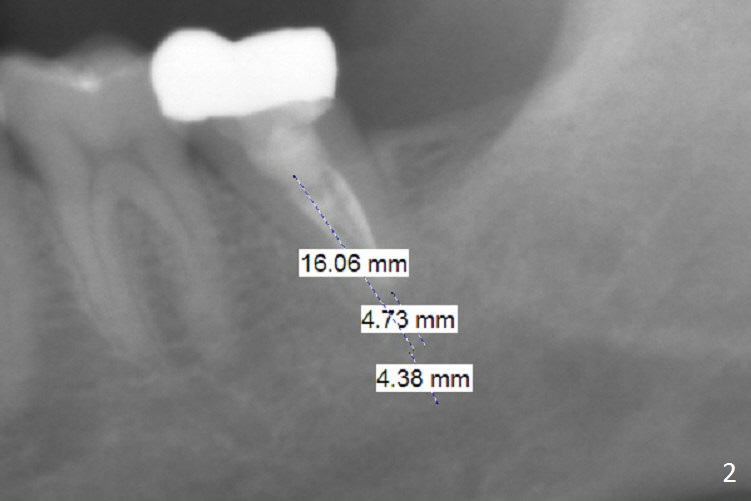

A 45-year-old man has had trouble with the tooth #18 for long time. First, the tooth needed RCT and crown retreatment several years ago (Fig.1). Now there is 2nd caries underneath the crown (Fig.2). After extraction and No Antibiotic, an IBS or Tatum implant will be placed (Fig.3).

Due to limited vertical height, the implant will be placed deep.